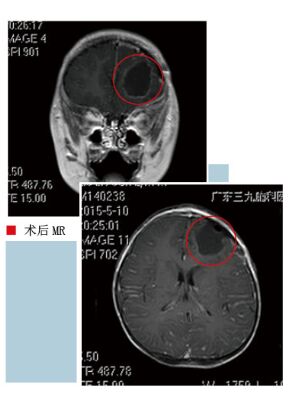

2015年4月20日患者突发神志不清,双眼上翻,四肢抽动。约3分钟后意识恢复清醒。到当地医院复查头部MRI及头部CT提示原来左额的病变体积较前明显增大。为进一步诊治家属带患儿来到了我科。入院时查体:生命体征平稳。发育正常,营养中等。神清。语言流利。双侧瞳孔=2.5mm,光反应灵敏。颈无抵抗。心肺腹(-)。四肢肌力V级,轻瘫试验-,共济失调-,各肢肌张力正常。生理反射存在,病理征未引出。入院后查MRI增强见左侧额叶占位病变,考虑肿瘤性病变,以胚胎性肿瘤可能性大(PNET可能)。经科室讨论,患儿颅内已有较大病灶,肿瘤可能性大,合并癫痫。目前患儿精神好,虽然年幼,但手术适应症明确。完善术前准备后于2014年5月8日在全麻下行“左额占位性病变切除术”。手术过程很顺利,病变完整切除。术后患儿恢复情况良好,3天后就可下床活动。病理证实为“(左额部)间变性室管膜瘤”。

本病例患儿年幼,颅内巨大占位,手术全切病变,效果满意。

术前MR考虑胚胎性肿瘤可能性大,术后病理证实为室管膜瘤。室管膜瘤来源于室管膜细胞,有神经上皮组织室管膜细胞的部位均可发病。脑室内室管膜瘤多见于第四脑室,其次为侧脑室,第三脑室少见。脑室外室管膜瘤以幕上多见,发生在脑实质内的室管膜瘤易发生囊变,脑室内肿瘤钙化较脑室外常见。幕上室管膜瘤多发生在脑实质内,最好发部位为顶叶,其次为额、颞叶。